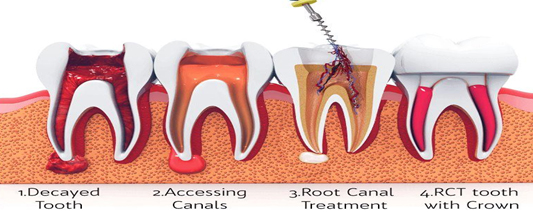

Can Root Canal Treatment Be Done In Single Sitting Without Any Pain?

Can Root Canal Treatment Be Done In Single Sitting Without Any Pain? Root canal treatment is the most reliable and…

Can Root Canal Treatment Be Done In Single Sitting Without Any Pain? Root canal treatment is the most reliable and…

Can Root canal treatment be painless? Generally, when the patient hears the word Root canal it makes them anxious. It’s…